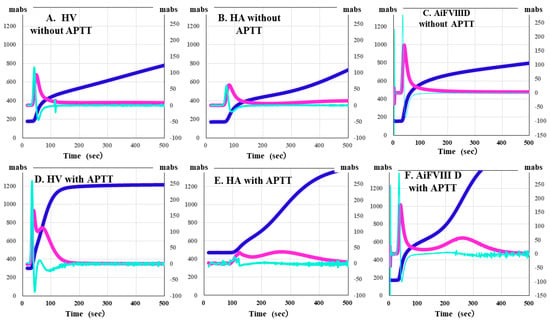

CWA-APTT was measured using patient PPP and HemosIL APTT-SP on an ACL-TOP system based on previously reported methods [29]. The CWA-small amount of tissue factor activation assay (sTF/FIXa) was performed using patient PRP and 2000-fold diluted HemosIL RecombiPlasTin 2G with saline solution including CaCl2 on an ACL-TOP® system [30]. The CWA-sTT of patient PPP was measured using an ACL-TOP® system with 0.2 IU of thrombin, which was diluted with 0.9% saline solution including CaCl2 [26,29]. CWA-sTT was measured with or without 16-fold diluted APTT-SP with 0.9% saline solution. CWA-sTT reflects thrombin burst caused by activated platelets and activated FVIII (FVIIIa), and when APTT reagent is added, it is more strongly affected by FVIIIa. In hemophilia A (HA), since the residual FVIII is extremely low, CWA-sTT is only minimally enhanced; in AiFVIIID, in comparison, it shows mild enhancement (Figure 1).

Figure 1.

Clot waveform analysis of clotting time determined using a small amount of thrombin. (A,D) healthy volunteer (HV); (B,E) hemophilia A (HA); (C,F) autoimmune factor VIII deficiency (AiFVIIID); (A–C) without APTT reagent; (D–F) with APTT reagent; APTT, activated partial thromboplastin time; navy line, fibrin formation curve; pink line, first derivative curve (velocity); light blue, second derivative curve (acceleration). In HV, the thrombin burst is enhanced by the addition of APTT reagent, whereas in HA, it is not enhanced, and AiFVIIID is slightly enhanced.

In the CWA-sTT, a small amount of FVIIIa is generated, which counteracts the effect of emicizumab, and since there is no incubation with the APTT reagent, it is considered not to be affected by emicizumab. In the CWA, three types of curves are shown [26,27]. The first represents the change in absorbance observed during the TT measurement, corresponding to the fibrin formation curve (FFC). The second is the first derivative of the absorbance peak (first DP), corresponding to the coagulation velocity. The third is the second derivative of the absorbance peak (second DP), corresponding to the coagulation acceleration.